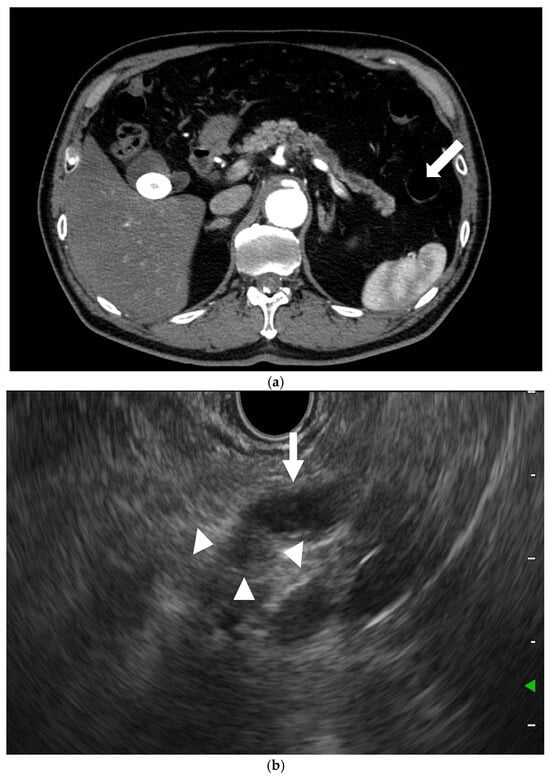

Moreover, the pooled sensitivity, pooled specificity, and area under the curve (AUC) of detection of PC with EUS in another metanalysis were 85%, 58%, and 0.8, respectively, when CT was missed [12]. Thus, EUS is a necessary tool for the diagnosis of PC that is not detectable by other modalities, particularly when PC is suspected due to indirect findings, such as a dilation of the main pancreatic duct (Figure 3).

Figure 3. EUS for detection of pancreatic cancers missed by CT. (a) CT: The main pancreatic duct dilation (arrow) was dilated, but no pancreatic lesion was detected. (b) EUS: A small hypoechoic lesion (9 mm; arrowhead), with dilation of the main pancreatic duct (arrow), was detected.